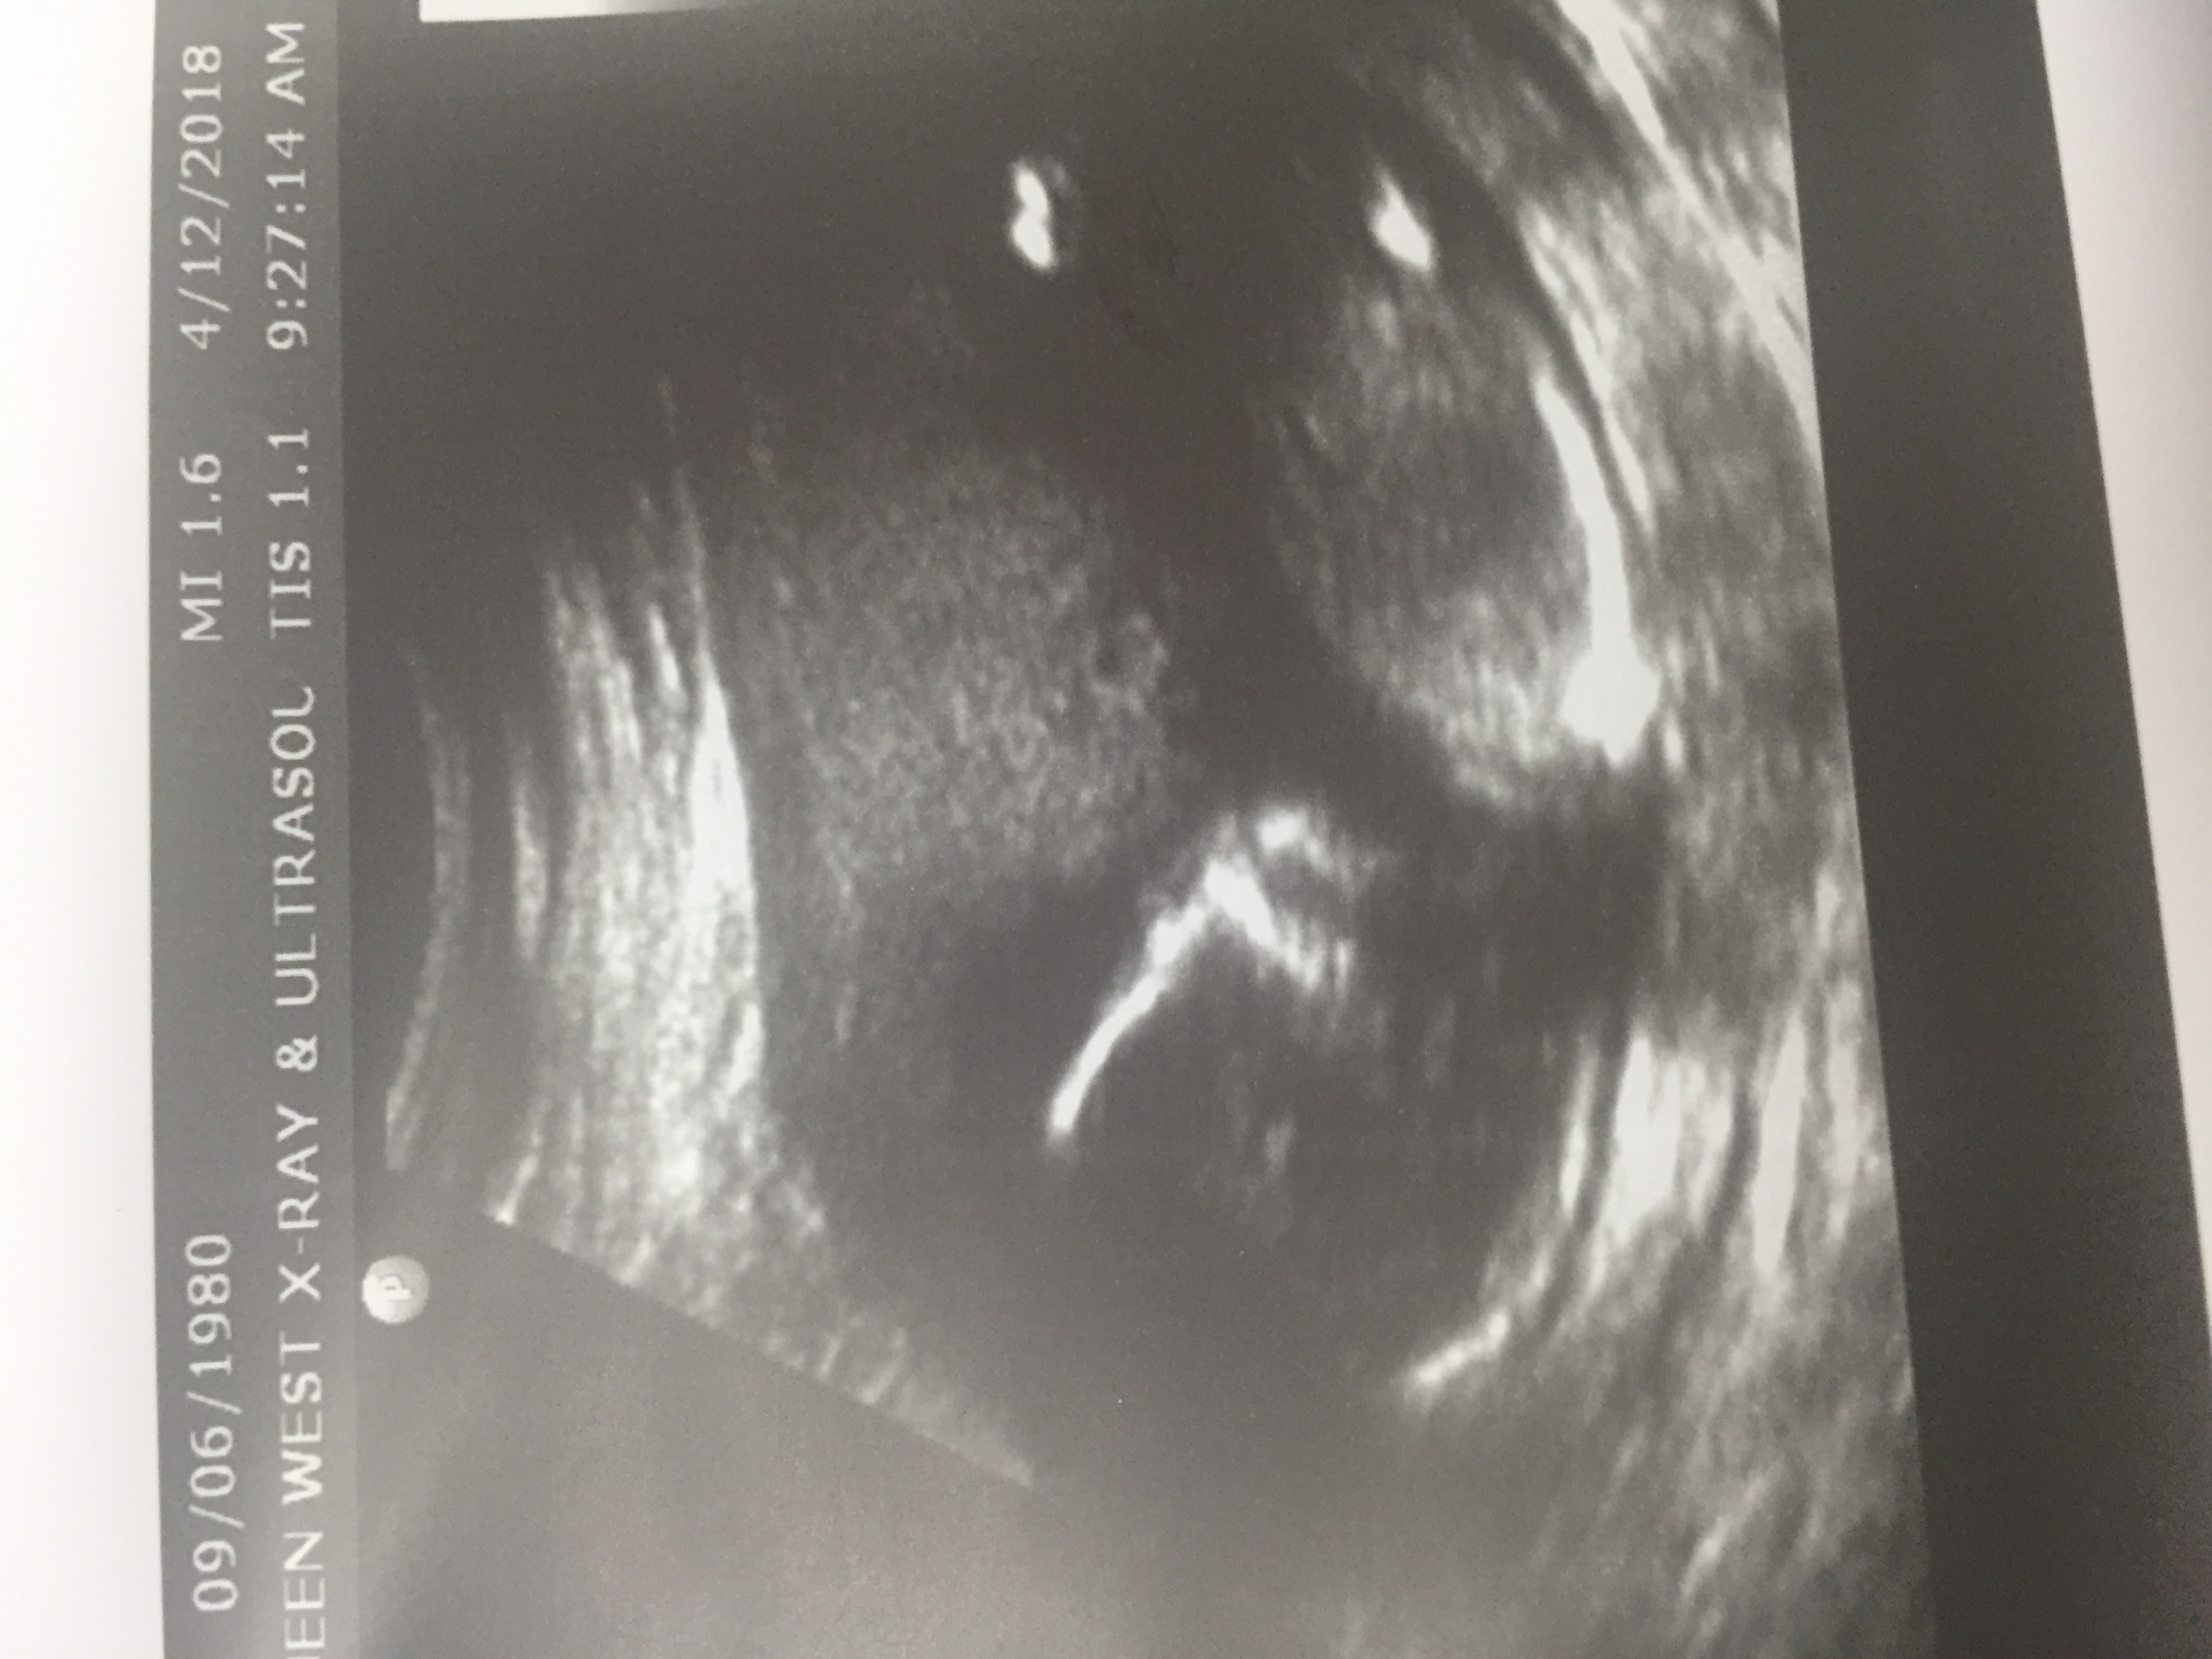

Ultrasound tech was v rude and rushed us through the whole thing..gave us one pic of the profile shot but I can't see any nub here ... any guesses at all?Attachment 39411Attachment 39411Attachment 39411